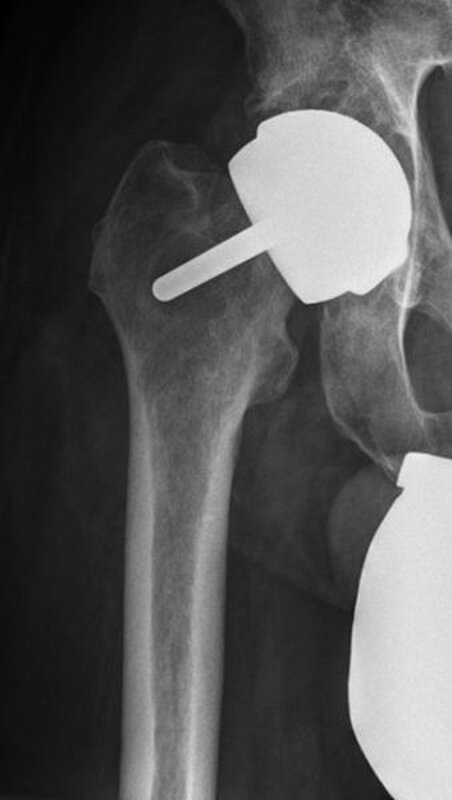

Kurze Vorgeschichte: Herr B., 56 Jahre, hatte Anfang des Jahres 2017 einen Oberflächenersatz des Femurkopfes rechtsseitig (McMinn Prothese, Abb. 1) implantiert bekommen. Mit Schmerzen in der rechten Hüfte erfolgte im Herbst 2017 erstmalig die Vorstellung in domo.

Eine Röntgenaufnahme des Beckens sowie der rechten Hüfte wurde durchgeführt. Hier wurde der Verdacht auf eine Implantatlockerung gestellt und ein CT der rechten Hüfte veranlasst. Hierbei zeigte sich neben den Lockerungszeichen im Bereich der Pfanne und des Implantates im Femur ein Verhalt zwischen Gluteus medius und maximus. Die Hüfte rechtsseitig wurde punktiert und ein multisensibler E. coli festgestellt. Es erfolgte die Planung zur stationären Aufnahme und Revision der rechten Hüfte.

Procedere: Nach der entsprechenden Vorbereitung erfolgte im September der Ausbau der McMinn-Prothese sowie die Resektion des Schenkelhalses, ein Débridement im Bereich des Hüftgelenkes sowie die Einlage eines Spacers (i.S. einer Copal Zementeinlage) in die Hüftpfanne und im Bereich des proximalen Femurschaftes (Girdlestone Situation). Ende November 2017 erfolgte 6 Wochen nach Spacer Implantation (Abbildung 2) eine erneute Wiedervorstellung zur Punktion des Hüftgelenkes als Vorbereitung auf den Prothesenwiedereinbau. Hierbei wurde erneut ein E. coli detektiert und eine antibiogrammgerechte Antibiose mittels Ciprofloxacin 500mg 1-0-1 fortgesetzte. Die Indikation zum Spacerwechsel wurde gestellt. Der Eingriff konnte geplant Anfang Dezember durchgeführt werden.